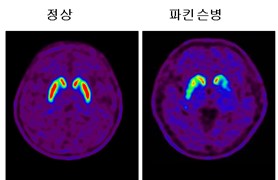

4. 파킨슨병의 진단과 치료